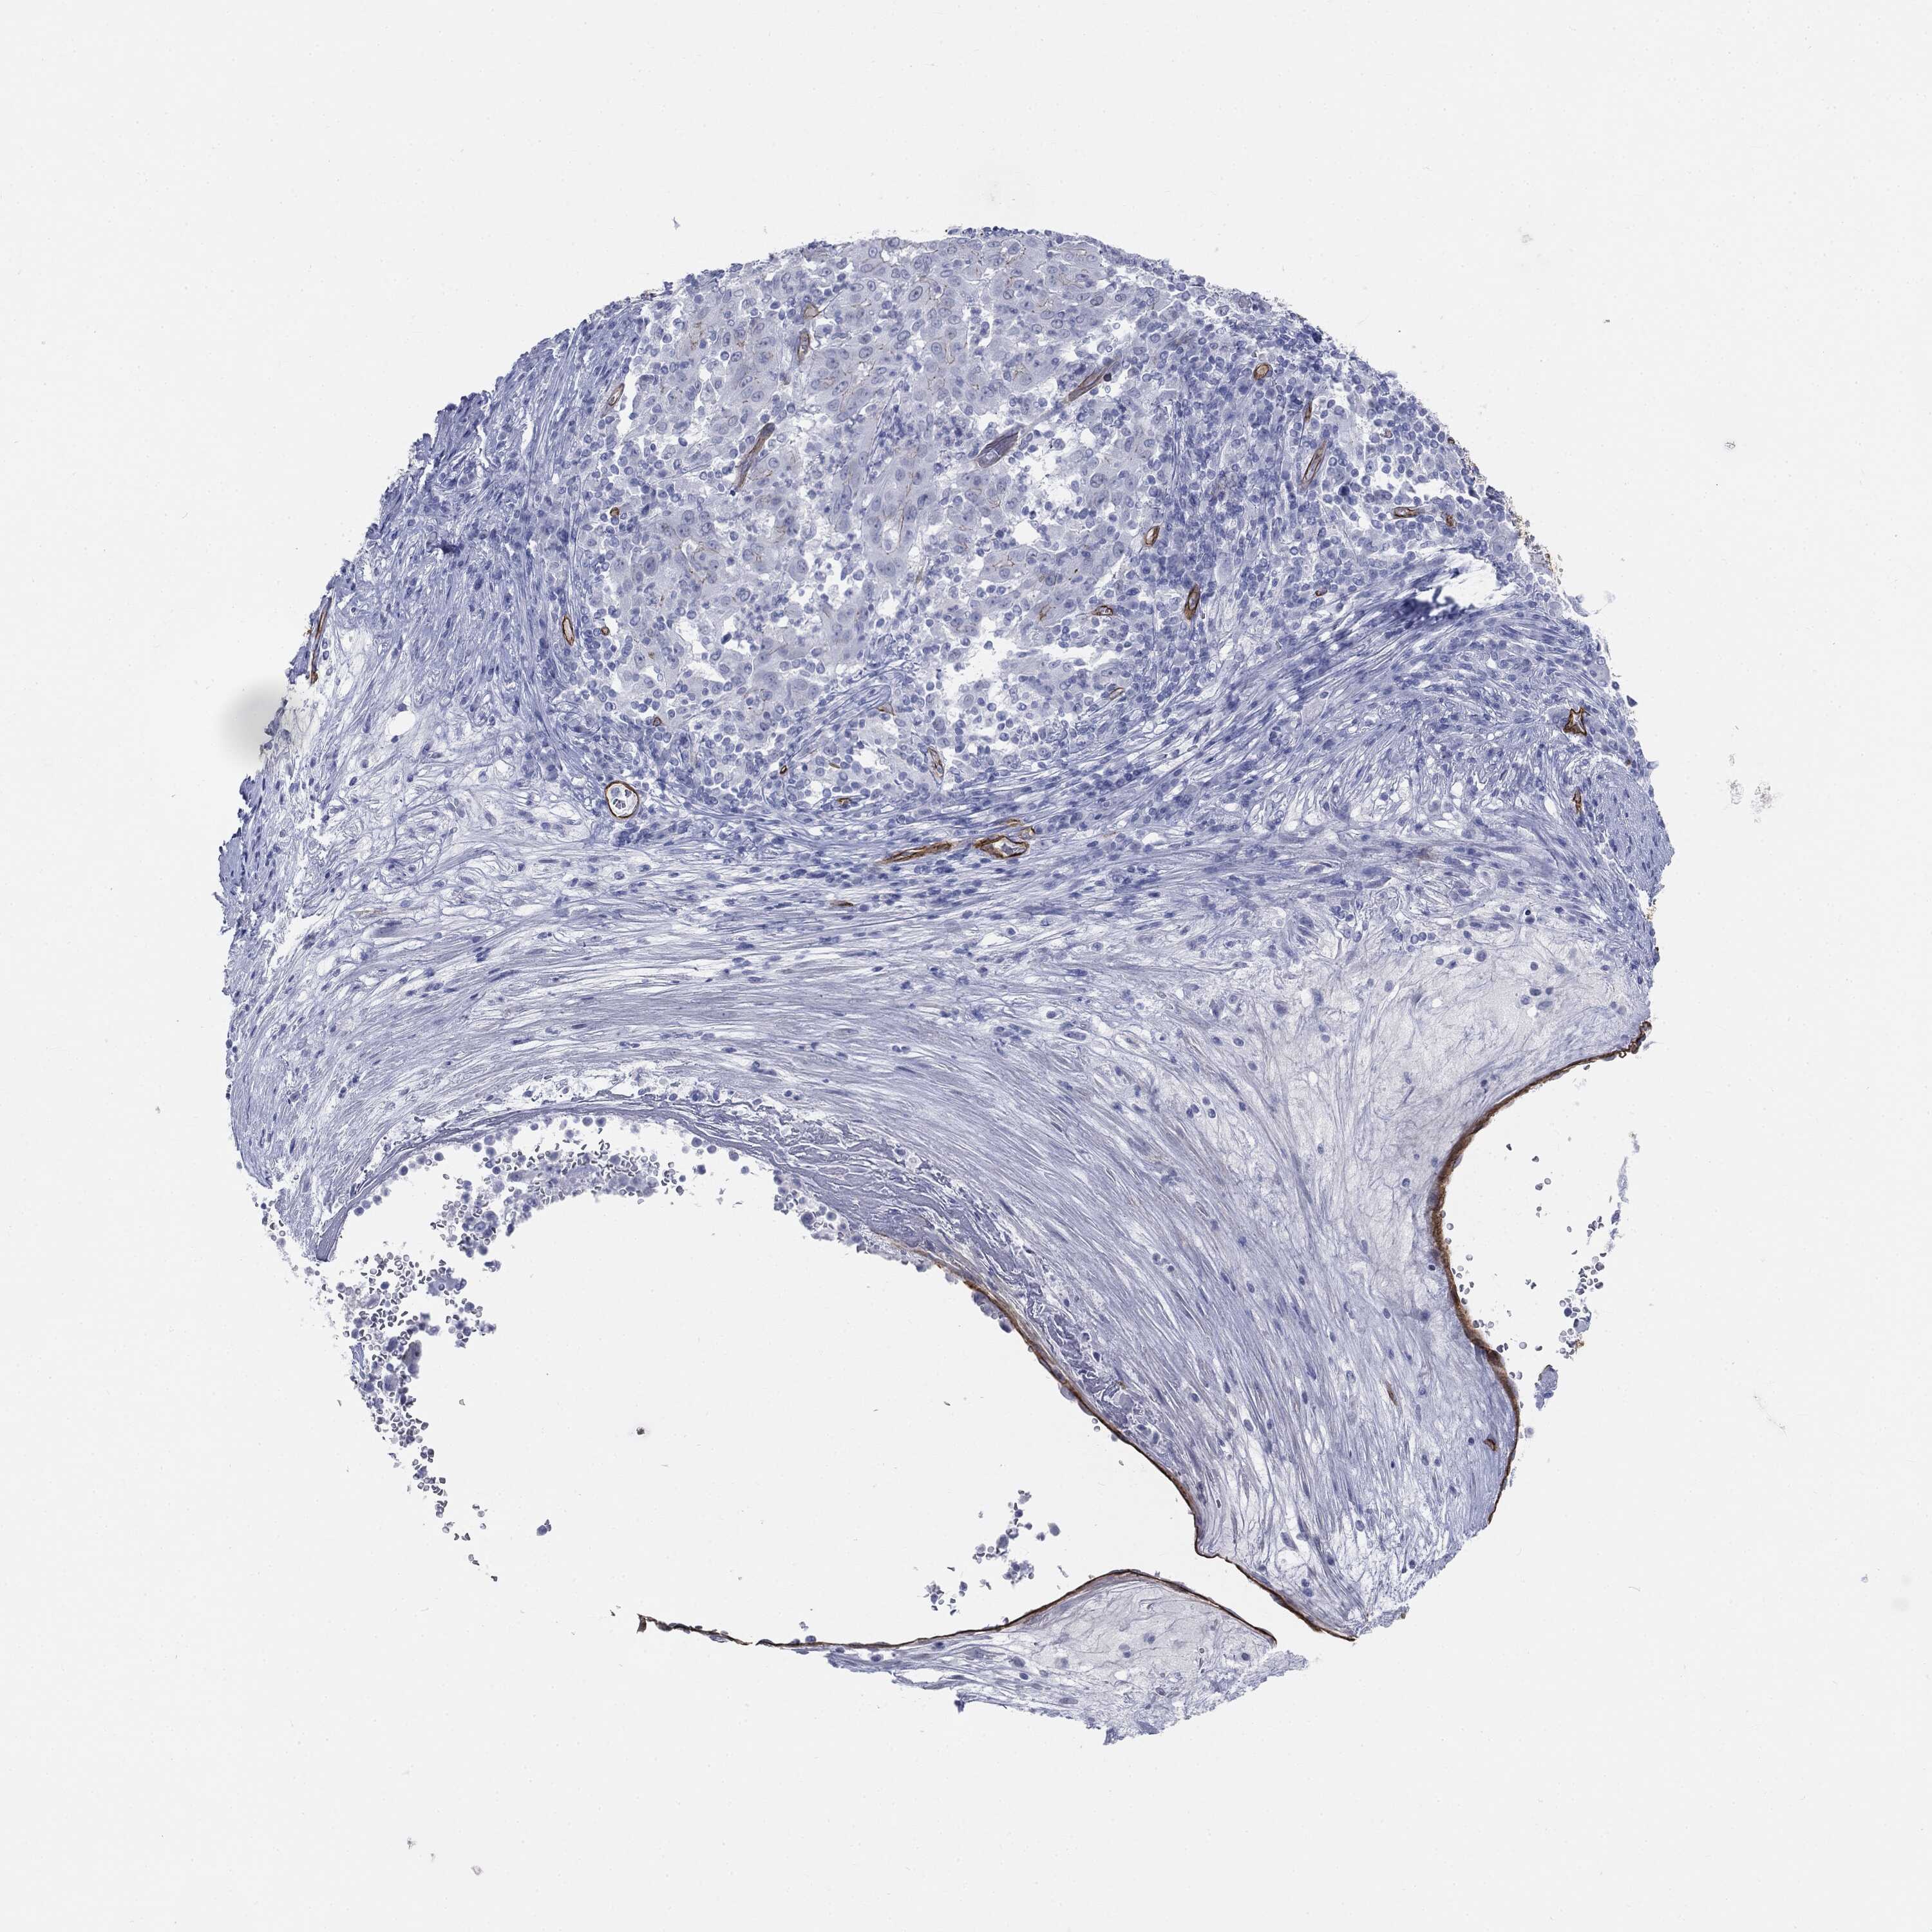

PANCREATIC CANCER - Protein expressioni

A mouse-over function shows sample information and annotation data. Click on an image to view it in a full screen mode. Samples can be filtered based on level of antibody staining by selecting one or several of the following categories: high, medium, low and not detected. The assay and annotation is described here.

Note that samples used for immunohistochemistry by the Human Protein Atlas do not correspond to samples in the TCGA dataset.

Antibody stainingi

Antibody staining in the annotated cell types in the current human tissue is reported as not detected, low, medium, or high, based on conventional immunohistochemistry profiling in selected tissues. This score is based on the combination of the staining intensity and fraction of stained cells.

Each image is clickable and will lead to virtual microscopy that enables deeper exploration of all samples and also displays staining intensity scores, fraction scores and subcellular localization as well as patient and tissue information for each sample.

Adenocarcinoma, NOS

Adenocarcinoma, metastatic, NOS